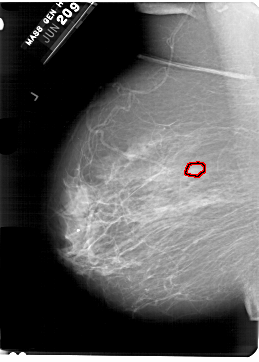

A_1329_1.LEFT_CC

FILE: A_1329_1.LEFT_CC.OVERLAY

TOTAL_ABNORMALITIES 1

ABNORMALITY 1

LESION_TYPE MASS SHAPE OVAL MARGINS ILL_DEFINED

ASSESSMENT 4

SUBTLETY 2

PATHOLOGY MALIGNANT

TOTAL_OUTLINES 1

BOUNDARY